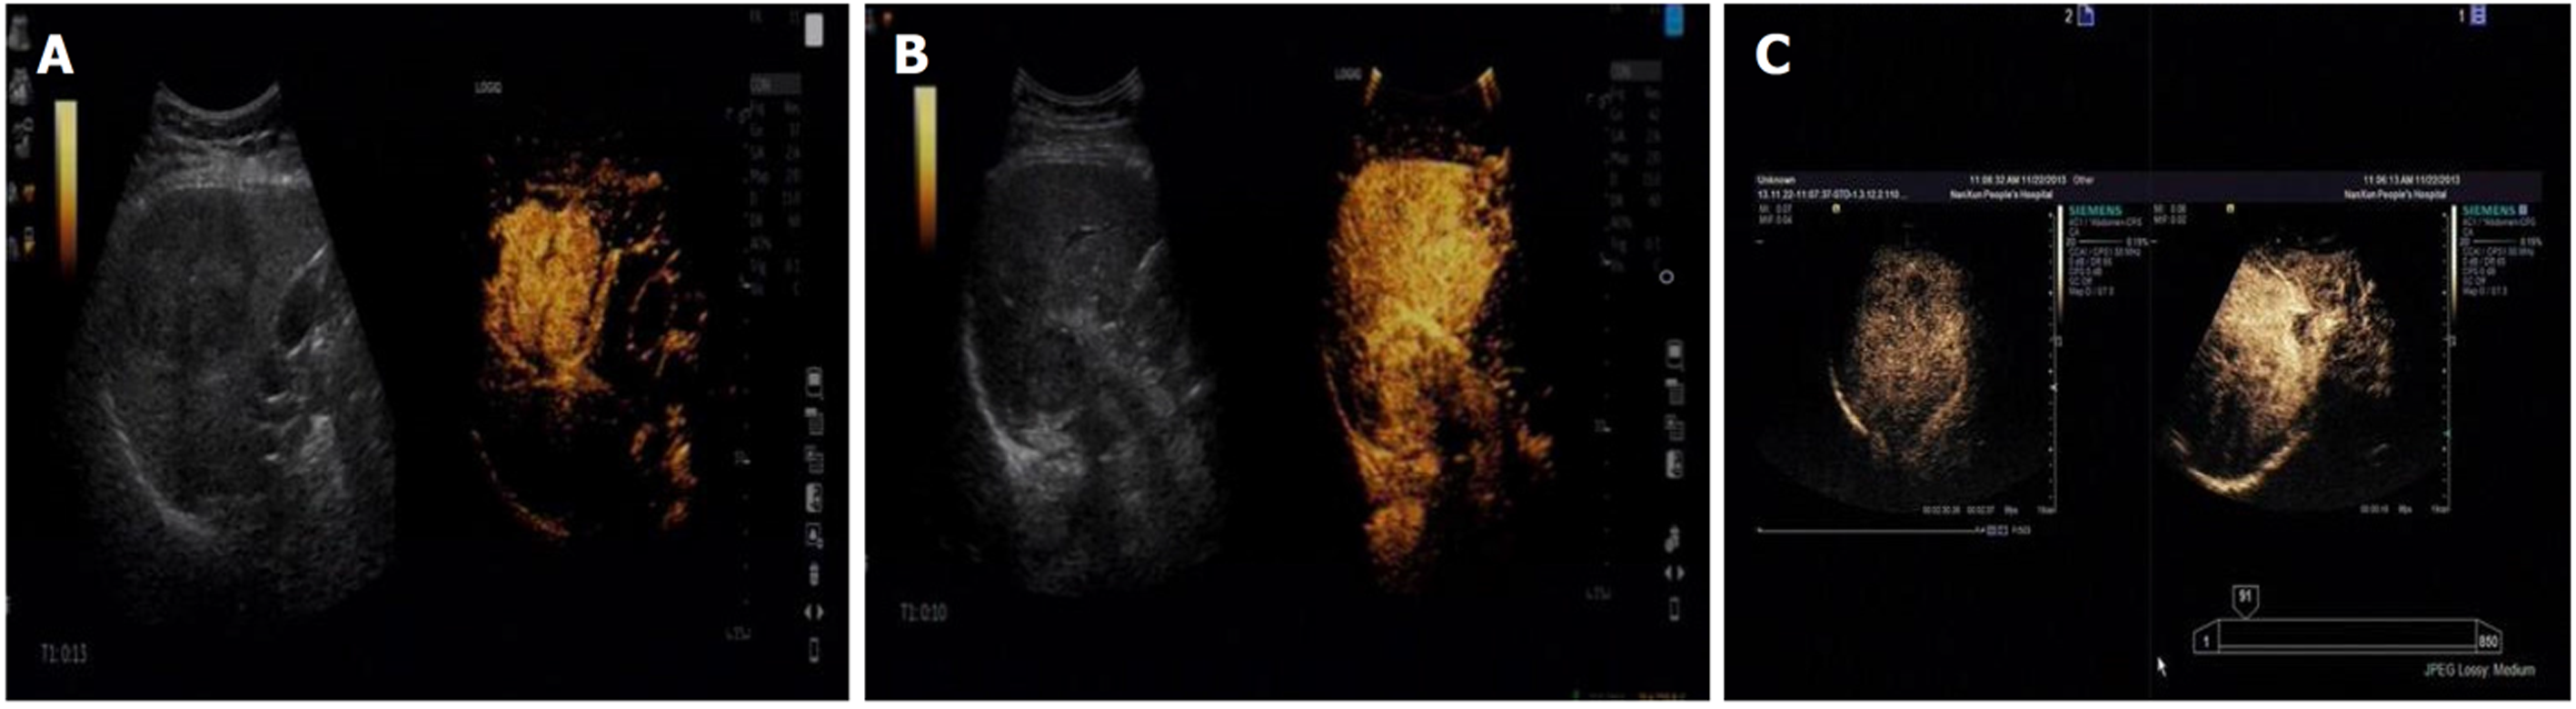

经超声造影检查结果显示, 原发性肝癌动脉相早期呈整体增强, 呈"快进快出"型表现, 边界多不规则, 具有周围血管围绕征, 肿瘤内血流信号杂乱, 肿瘤后方回声无明显变化, 少数后方回声轻度增强; 而肝转移瘤超声造影特征主要呈强回声、不规则形状、快速显影、血供丰富等, 动脉相早期大部分呈整体增强, 周边呈厚圈状增强, 中心部位无增强, 廓清后均呈"黑洞"表现. 见图1和图2.